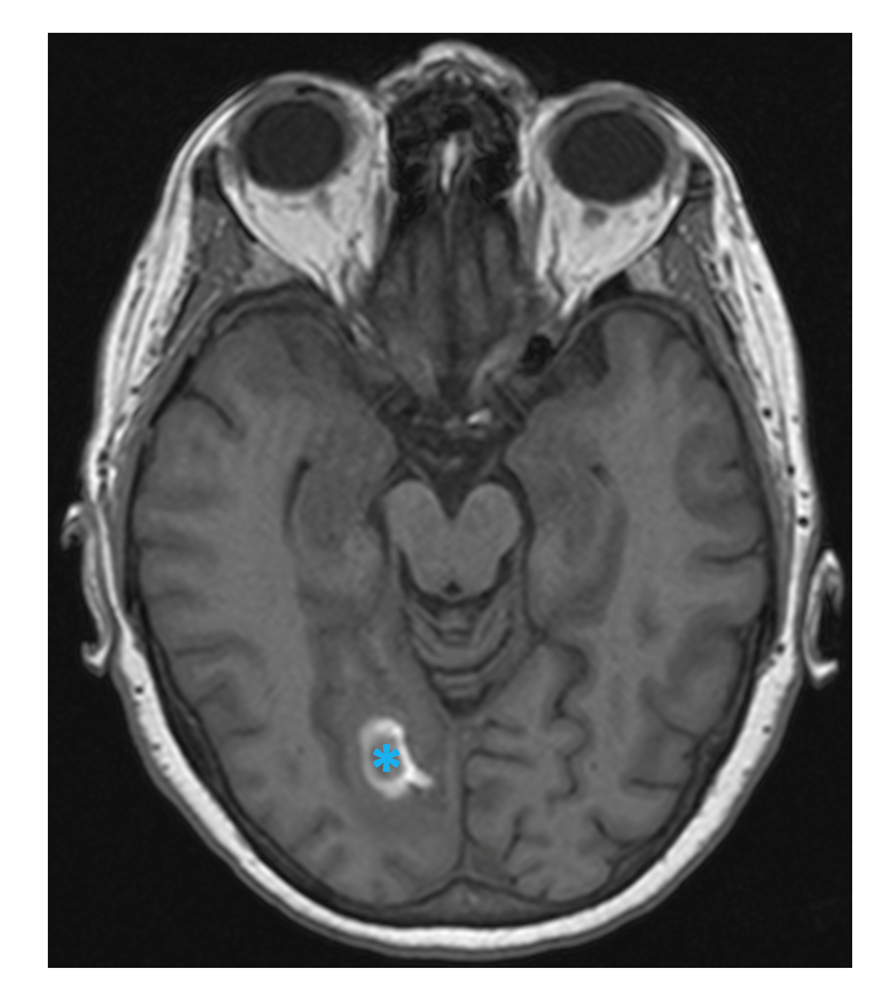

A brain MRI study displayed an extensive CVST, with main involvement of the right transverse and sigmoid sinuses (Figure 1), and extension to the straight sinus and vein of Galen. There were infarction signs in the thalamus (Figure 2) and in the right occipital region, with associated bleeding in this zone (Figure 3).

Fig. 3 MRI T1-weighted image showing signal disturbance in the right occipital lobe with hyperintense peripheral halo, corresponding to hemorrhagic infarct (blue asterisk, axial view).